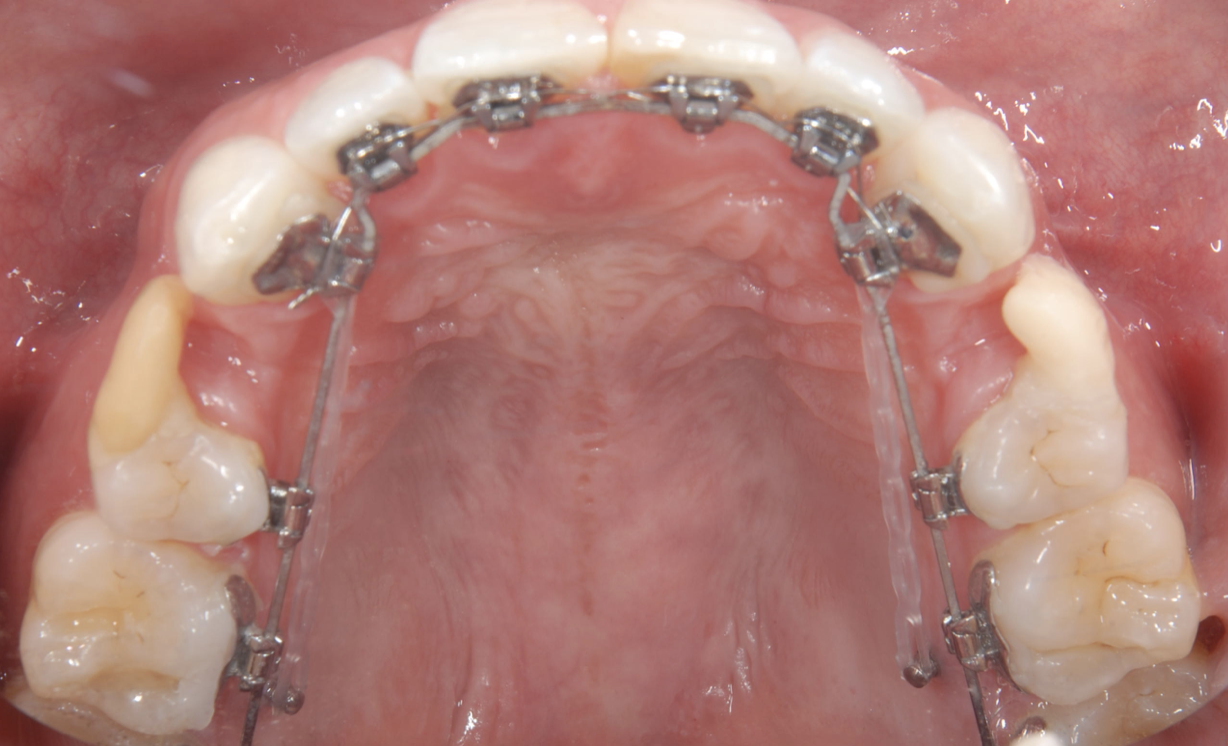

上顎の口蓋部の正中付近に2本スクリューを埋入して大きな固定ステーションとして行う方法や歯に近い部分に埋め込んで固定源にする方法などがあります。

正中部に埋入する場合には歯と十分に距離がありますので位置を変える必要はありませんし、前歯も小臼歯も奥歯の大臼歯もアプローチが可能になります。しかし、装置の厚みがありますので舌感が悪く、発音にも影響が出ることがあります。